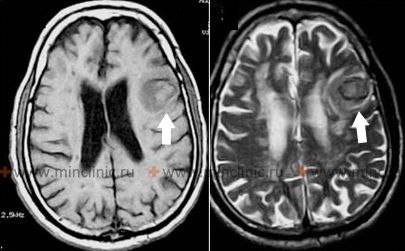

როგორც კი პოპულაციაში უმჯობესდება ჰიპერტენზიის კონტროლი, იზრდება ინტრაცერებრული სისხლჩაქცევების შეფარდებითი პროპორცია, რომლებიც ხდება ტიპიური ღრმა ჰიპერტენზიული ლოკაციების (ბაზალური განგლიები, თალამუსი) მიღმა [1]. ეს სისხლჩაქცევები, რომლებსაც ხშირად უწოდებენ "ლობარულ სისხლჩაქცევებს", ტვინის ვიზუალიზაციაზე (მრტ ან კტ) ტიპიურად ჩნდებიან როგორც სისხლის ოვალური ან მომრგვალებული დაგროვება ძირითადად ცერებრალური წილების სუბკორტიკალურ თეთრ ნივთიერებაში [1, 2]. მიუხედავად იმისა, რომ ქრონიკული ჰიპერტენზია შეიძლება იყოს ხელშემწყობი რისკ-ფაქტორი, განსაკუთრებით ცერებრალური ამილოიდური ანგიოპათიისთვის (CAA), ის ხშირად *არ არის* პირველადი ძირითადი მიზეზი და ლობარული სისხლჩაქცევის მქონე ბევრ პაციენტს არ აქვს მნიშვნელოვანი ჰიპერტენზიის ისტორია[1, 3]. შემთხვევების მნიშვნელოვან ნაწილში იდენტიფიცირებულია სპეციფიკური ძირითადი სტრუქტურული დაზიანებები ან მდგომარეობები, მათ შორის [1, 2]:

CAA არის სპონტანური, ხშირად განმეორებადი, ლობარული სისხლჩაქცევის მთავარი მიზეზი ხანდაზმულებში [3]. CAA-ს მქონე პაციენტებს ასევე შეიძლება აღენიშნებოდეთ სხვა ვიზუალიზაციის მიგნებები, როგორიცაა ცერებრალური მიკროსისხლჩაქცევები (უპირატესად ლობარულ ლოკაციებზე), კორტიკალური ზედაპირული სიდეროზი და თეთრი ნივთიერების ჰიპერინტენსივობები მრტ-ზე [2, 3].